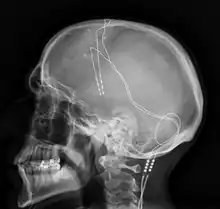

La stimulation cérébrale profonde consiste à implanter des électrodes au niveau des ganglions de la base. Elle a montré des résultats prometteurs[53],[62]. Ce traitement est limité aux formes les plus sévères de la maladie du fait de son caractère invasif et du risque d'infection liée à l'opération.